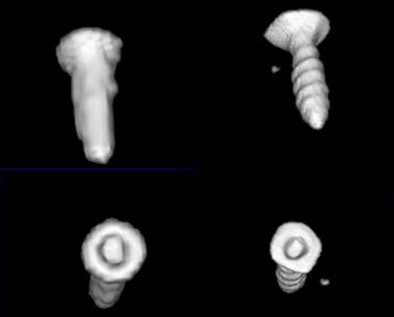

| The flat-panel VCT images of the skull base at right were rated significantly higher in image quality compared to 16-slice MDCT images of the same regions at left, by two readers rating 21 features independently. Images (from top to bottom) include stapes and ovale window niche (above), facial nerve canal (below), maxillofacial region, and implanted microscrews (bottom). All images courtesy of Dr. Sönke Bartling. |

"The same holds true for small and especially thin structures within the maxillofacial region, for example the medial limitation of the orbital cavity is much better delineated in flat-panel-based volume CT," Bartling said. And the technique produces fewer metal artifacts, he added.

"Flat-panel volume CT of the whole human skull base is possible, and we have better delineation of small high-contrast structures and thin high-contrast structures, and improvement is possible in surgical planning, navigation and maybe diagnostic imaging," Bartling concluded.